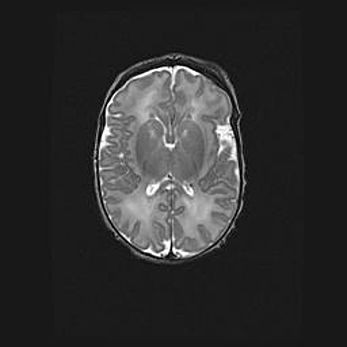

Церебральная ишемия II.

Возраст: 5 дней

Вес: 3400 г

Пол: женский

Окружность головы: 35 см

Срок гестации: 39 недель

Церебральная ишемия – это заболевание, характеризующееся недостаточностью (гипоксией) либо полным прекращением (аноксией) снабжения мозга кислородом по причине закупорки одного или нескольких сосудов. Это приводит к  что метаболическим расстройствам различной степени тяжести в тканях головного мозга, развитию коагуляционных некрозов и гибели нейронов.